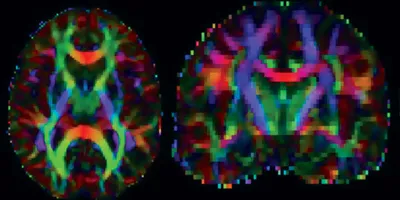

Picture credit: Dr Mark Bastin, Brain Research Imaging Centre (BRIC)